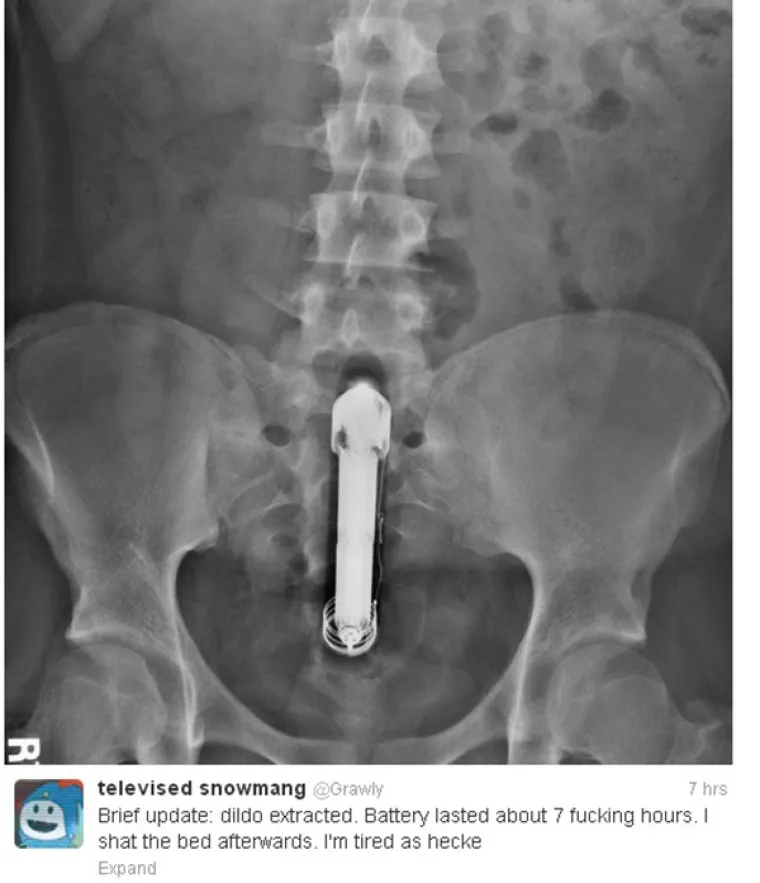

Zapeo mu vibrator u guzi, a on svoje iskustvo tweetao cijelom internetu. Za znanost...

Foto: Twitter